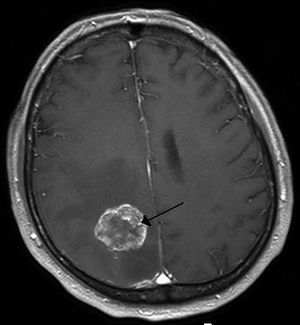

| Brain metastasis in the right cerebral hemisphere from lung cancer shown on T1-weighted magnetic resonance imaging with intravenous contrast. (L=left, P=posterior, back of the head) | |